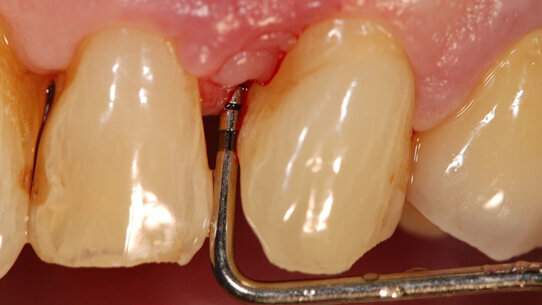

La tecnica Soft Tissue Wall è raccomandata per il trattamento di difetti infraossei nell’area estetica, quando uno dei denti coinvolti presenta anche una migrazione apicale del margine gengivale libero.

In questo approccio, un’incisione orizzontale è realizzata alla base delle papille interdentali ed estesa un dente mesiale e distale dal difetto infraosseo. Viene quindi elevato un lembo a tutto spessore trapezoidale (con la base più larga posizionata apicalmente). La restante porzione vestibolare delle papille viene conservato e disepitelializzato per creare un letto di tessuto connettivo stabile su cui il lembo può essere suturato. La papilla sopra il difetto infraosseo è sezionata alla base e l’intero tessuto molle interprossimale sopracrestale è elevato al fine di ottenere un adeguato accesso al difetto.

Per eliminare la tensione muscolare e consentire lo spostamento coronale del lembo viene poi eseguita una dissezione, sia tagliente che smussa, della mucosa vestibolare. Il rilascio del lembo e la sua mobilizzazione sono ritenuti sufficienti quando la porzione marginale del lembo è in grado di raggiungere passivamente un livello più coronale alla giunzione amelo-cementizia (CEJ) e di coprire le papille anatomiche precedentemente disepitelializzate.

Per stabilizzare e riposizionare coronalmente il lembo vestibolare vengono utilizzate due suture sospese. La superficie radicolare può essere condizionata per rimuovere lo smear layer e per ottenere una superficie priva di residui organici. Possono ora essere applicati nel difetto elementi bioattivi come derivati della matrice dello smalto (Emdogain®, Straumann CH) o biomateriali riempitivi in combinazione o meno a fattori di crescita. La chiusura primaria della papilla interdentale sul difetto osseo priva di tensione è realizzata con una sutura a materassaio orizzontale interna, e le incisioni verticali sono chiuse con suture semplici.